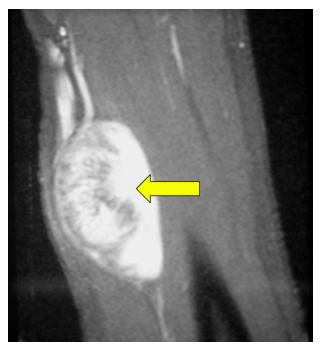

• • The work-up for Schwannoma often consists of a physical examination, X-ray, MRI, CT, and bone scans. The diagnosis is often confirmed with a biopsy, which samples the tumor for further analysis.

Radiographic imaging is used to help form a diagnosis. These include X-Ray, MRI, CT and Bone Scans

An example of an MRI is shown.

Schwannoma MR